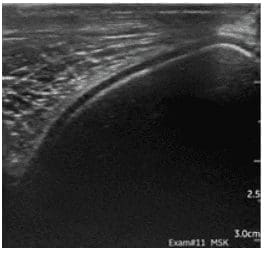

A. In short, yes! Incredibly so, in fact. It is important to note that they have been designed with a specific purpose in mind. Namely, point-of-care ultrasound (POCUS), and the flexibility they offer is, frankly, stunning. Typically, they offer two or more transducer options. Either by virtue of interchangeable ‘heads’, or being ‘double-ended’, with different transducer types on each end. Wireless transmission of image data to a smart device (phone, tablet, etc.) enables viewing anywhere, and image quality is surprisingly good. They wouldn’t replace a traditional high-end system, certainly, but in the context of the relatively recent rise in popularity of POCUS, they are something of a game-changer. Light, portable, robust, low-cost, and high-quality, I suspect it won’t be long before they’re as ubiquitous and indispensable as a stethoscope.

Equine SDFT & DDFT, GE Vscan Air Equine medial trochlear ridge (stifle), GE Vscan Air